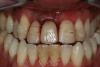

Fig 12. Six months after cementation.

Figure 12